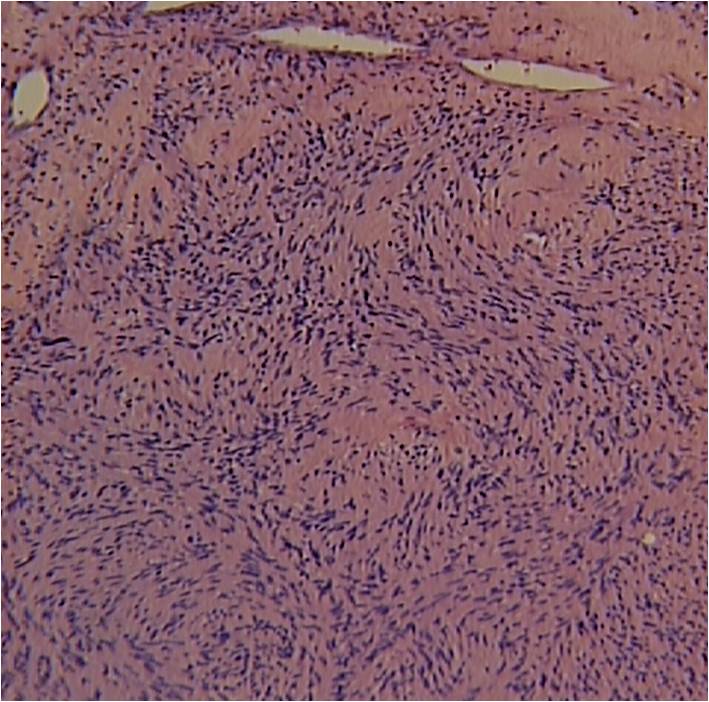

Microscopic Pathology

• Usually uninodular masses

• Surrounded by fibrous capsules consisting of epineurium and residual nerve fibers

• Distinct Pattern of alternating Antoni A and B areas

o Antoni A Area: Cellular area arranged in short bundles or interlacing fascicles

Spindle cells with wavy appearing nuclei. (Fig. 5 & 6)

o Antoni B Area: Less cellular and more myxoid (Fig. 7)

Fig. 5-7 Microscopic Pathology demonstrates 2 different patterns; Antoni A area with spindled hypercellular distribution with wavy appearing nuclei (Fig 5 & 6A) that palisades, known as Verocay Bodies (Fig 6B). Antoni B area is less cellular and more myxoid (Fig 7) than the Antoni A area. Mitotic activity is not visible.